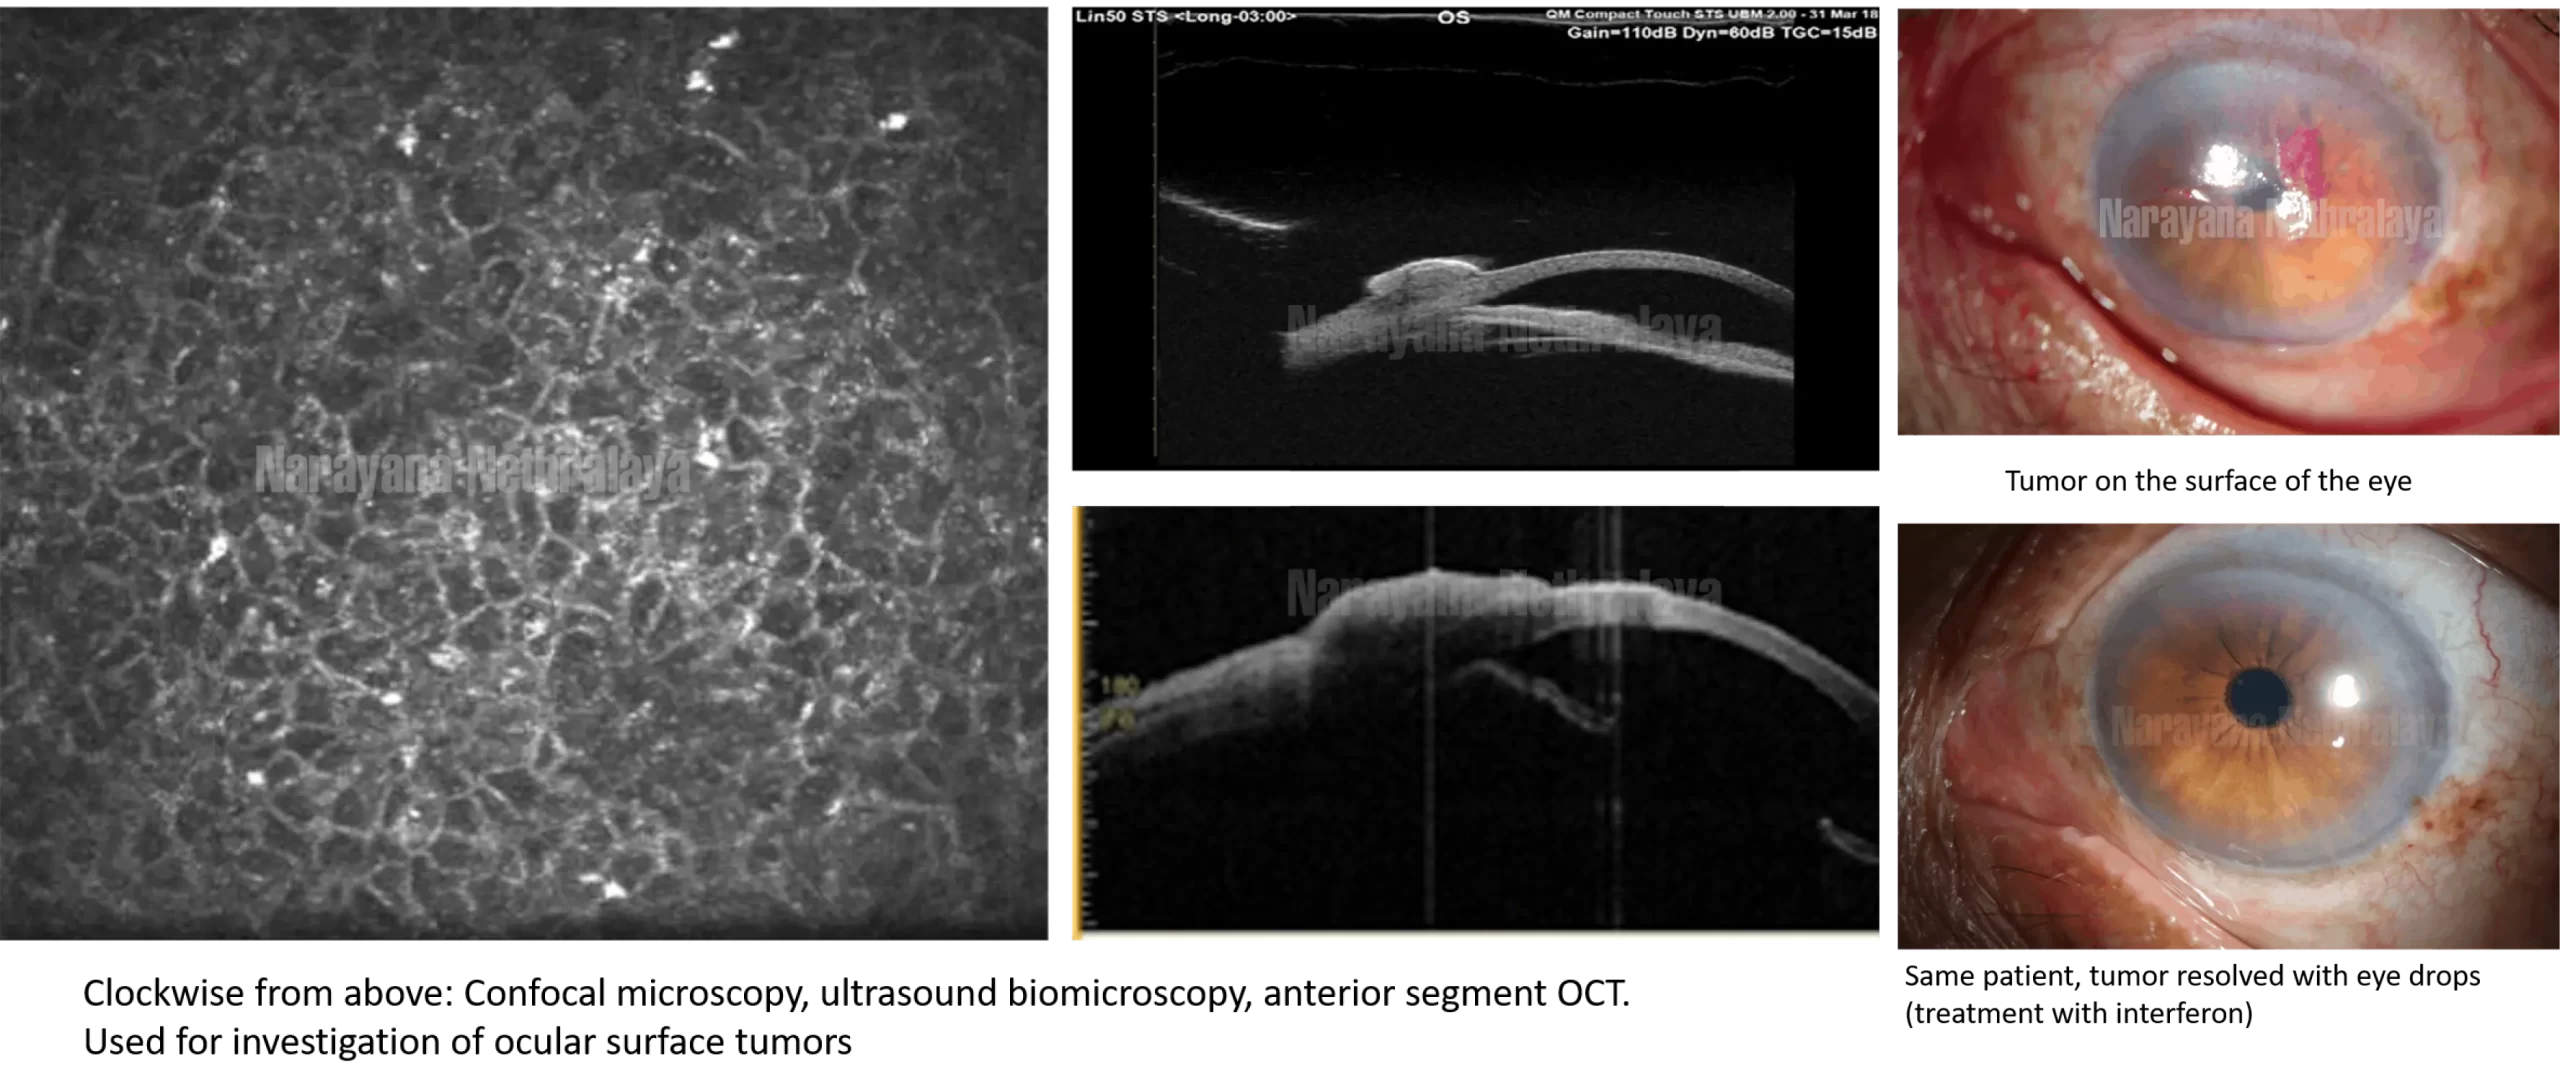

Most tumors are identified during examination by the ocular oncologist.  A coloured dye can be applied to the eye to further identify the tumor ( Rose Bengal or Lissamine Green). The  tumor is photographed in high resolution using slit lamp photography, so that its progress can be checked. UBM (Ultrasound biomicroscopy) and anterior segment OCT are performed to check whether the tumor is only on the outer surface of the eye, or is it starting to extend inside.

Eyedrops – eye drops are mixed in the department from specific injections such as interferon alpha 2 B, mitomycin C, and 5 Fluoro uracil. The term for this treatment is ‘topical chemotherapy’. This is particularly useful for tumors covering the black part of the eye or large tumors. The treatment continues for several months, with testing regularly to check for progress.

A conjunctival tumor is a growth over the white part of the eye. It may initially appear as a reddish layer growing over the white part of the eye, or a whitish growth over the black part of the eye. It can also be brown or black in colour.

Some conjunctival tumors can be malignant, that is, dangerous. It can spread over the black part of the eye, and even grow inside the eye, thereby endangering the vision.